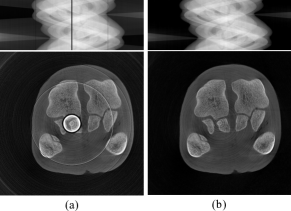

Figure 7: Comparison experiments with simulated data. (a) Normalization method. (b) Regularization method. (c) W-FFT method. (d) FFT method. (e) Combination method. (f) Proposed method. The display range is [0, 1] for the sinogram and [0, 0.0015] for the CT images.

The experimental results are shown in Fig. 7, which presents the corrected sinograms and provides a quantitative comparison with the reference sinogram regarding PSNR and SSIM. Higher scores indicate better consistency with the reference sinogram. The second row displays the profile curves of the 200th row, with the green curve representing the reference profile and the red curve showing the predicted profile. The third row shows the reconstructed images and their local zoom-in views.

Zoom-in views (a) to (d) in Fig. 7 reveal some ring artifacts, indicating limitations in suppressing defective pixels with these methods. In contrast, the zoom-in views in Fig. 7 (e) and Fig. 7 (f) show reduced ring artifacts, with Fig. 7 (f) exhibiting the least. The image in Fig. 7 (e) presents other types of artifacts. In the profile curves of the 200th row, Fig. 7 (a) to Fig. 7 (d) show noticeable deviations from the reference profile curve in columns 400 to 404. The quantitative evaluation results indicate that the PSNR value of the predicted IS in Fig. 7 (f) performs best among all compared methods, suggesting an advantage in signal fidelity and the suppression of stripe artifacts. Quantitative evaluation results indicate that the SSIM value of Fig. 7 (f) is the highest among all the compared images, demonstrating that this method offers significant advantages in signal fidelity and noise suppression.

In summary, the proposed method performs well in suppressing stripe artifacts and accurately estimating the IS values of defective pixels, thereby improving the quality of image reconstruction to a certain extent.